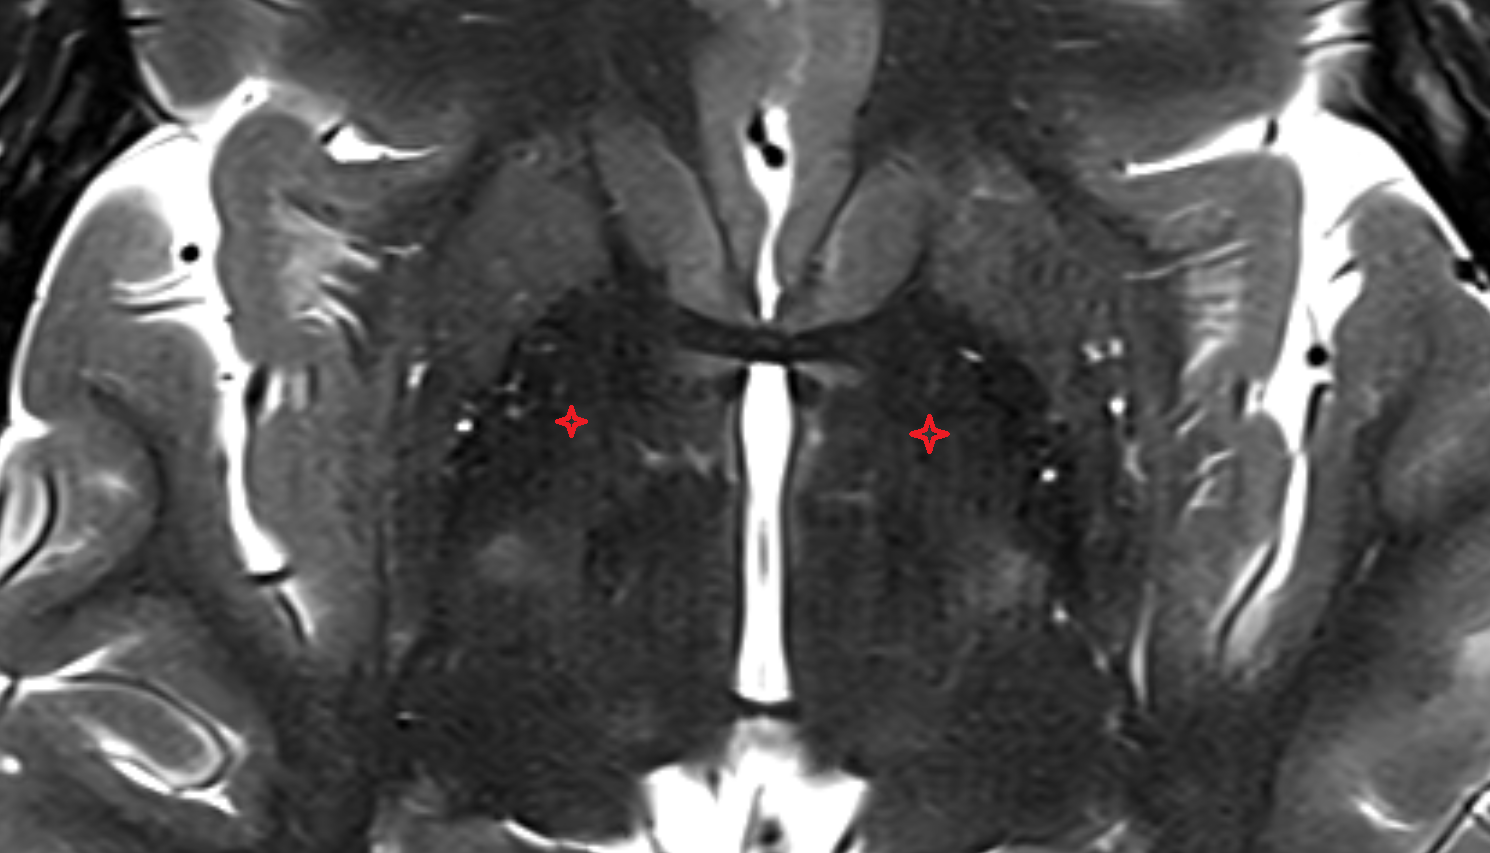

- Dentate nucleus

- Thalamus